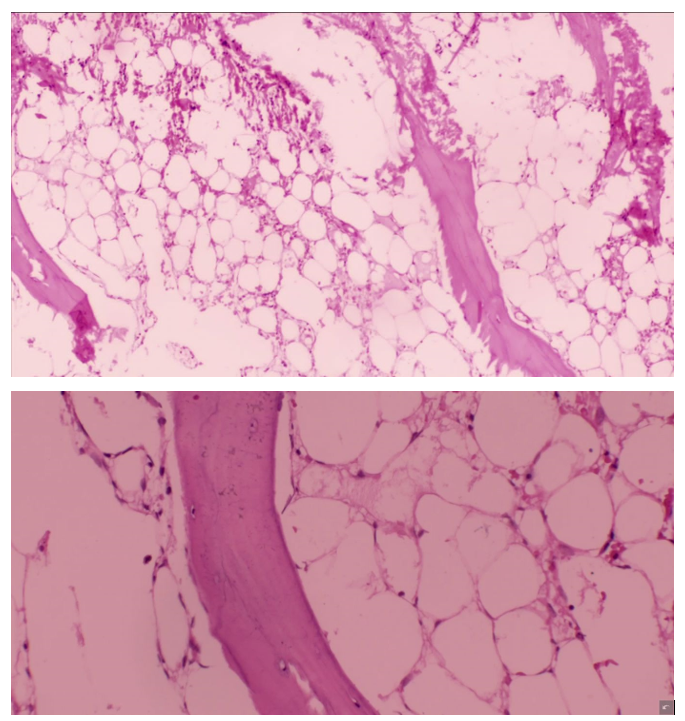

Intususcepción secundaria a divertículo de Meckel. reporte de caso

Luis Roberto Hernández Mercado, Sergio Iván Granados Torres, Joaquín Enrique Villamizar Zúñiga

Diverticulitis en colon sigmoides de una niña de 9 años. Reporte de caso

José Alfredo González-Ortiz, Luis Enrique Toxqui-Merchant